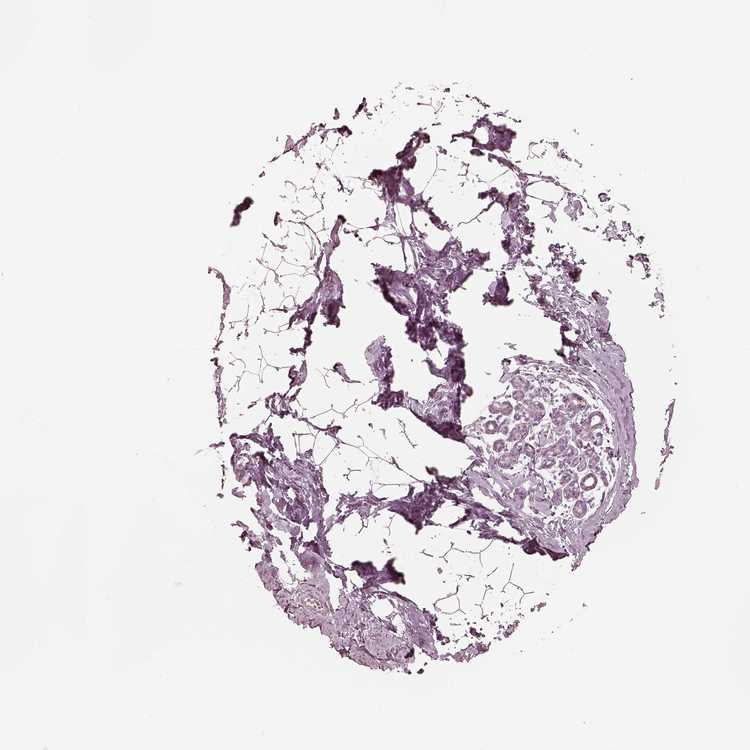

BREAST - HPA RNA-seqi

The RNA-seq details section shows detailed information about the individual samples used for the transcript profiling and results of the RNA-seq analysis.

Information about each individual sample is listed below, including gender, age, a tissue section image and estimated fractions of cell types. nTPM (normalized transcripts per million) values give a quantification of the gene abundance which is comparable between different genes and samples.

Female, age 52

Breast sample 373

nTPM: 0

Cell types%

Glandular cells:

15

Adipocytes:

5

Other cell types:

80